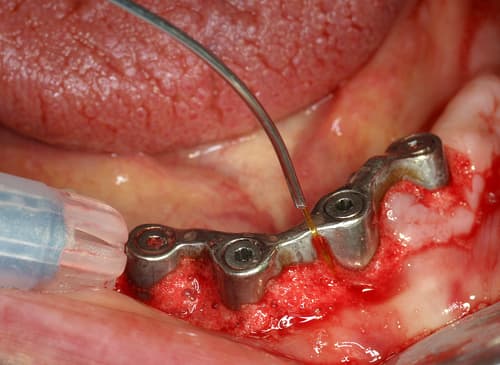

Le laser peut être utilisé dans la prise en charge des péri-implantites, avec un objectif de décontamination des tissus infectés autour des implants.

Per-opératoire